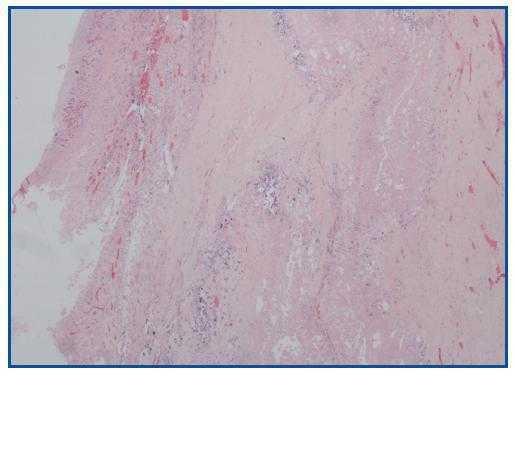

La necropsia demostró un proceso fibrosante sistémico (Figuras 1-4), con afectación de pelvis menor, retroperitoneo, en coraza alrededor de riñones, glándulas suprarrenales y páncreas, abarcando espacio periesplénico y perihepático; y mediastínico, en coraza alrededor de pericardio, arco aórtico y grandes vasos; y paquipleuritis derecha con fibrosis calcificada. Se apreciaron también: pancreatitis crónica fibrosa asociada, atrofia testicular, fenómenos de enfermedad aterombólica, hipertrofia ventricular izdª, y hepatopatía fibrosa crónica, en el contexto de un paciente con arteriosclerosis generalizada severa, con repercusión renal -nefroangiosclerosis bilateral con atrofia renal derecha, encefálica –infarto antiguo quístico izquierdo a nivel de ínsula-, y de colon –colitis isquémica rectosigmoide.

Figura 4.